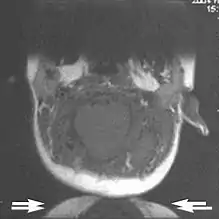

Fig. 6. Wrap-around artifacts.[1]

Fig. 7. Wrap-around artifacts.[1]

A wrap-around artifact also known as an aliasing artifact, is a result of mismapping of anatomy that lies outside the field of view but within the slice volume.[4] The selected field of view is smaller than the size of the imaged object. The anatomy is usually displaced to the opposite side of the image (Figs 6 and 7). It can be caused by non-linear gradients or by undersampling of the frequencies contained within the return signal.[1] The sampling rate must be twice the maximal frequency that occurs in the object (Nyquist sampling limit). If not, the Fourier transform will assign very low values to the frequency signals greater than the Nyquist limit. These frequencies will then ‘wrap around’ to the opposite side of the image, masquerading as low-frequency signals. In the frequency encode direction a filter can be applied to the acquired signal to eliminate frequencies greater than the Nyquist frequency. In the phase encode direction, artifacts can be reduced by an increasing number of phase encode steps (increased image time). For correction, a larger field of view may be chosen.[1]